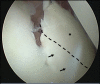

Glenoid articular cartilage lesion is a rare complication following traumatic anterior dislocation of the shoulder. We report the case of a 14-year-old male rugby player with traumatic anterior shoulder instability, an extensively flapped lesion on the glenoid articular cartilage, and an osseous Bankart lesion. Arthroscopic findings revealed that the glenoid cartilage was flap-detached, extending from the anteroinferior to the center. Repair of the osseous Bankart lesion using suture anchors and resection of the unstable peripheral part of the cartilage was performed arthroscopically. The main region of the injured articular surface was left untouched. During postoperative follow-up, absorption of the glenoid articular surface near the suture anchor holes was identified. Arthroscopic examination three months post-surgery showed that the flap detached lesion of the residual cartilage was stable and appeared adapted on the glenoid surface. The resected area was covered by fibrous tissue. A follow-up computed tomography scan revealed that the osseous lesion was united. The patient returned to his previous sports capacity eight months following the operation. At the 2-year-follow-up, magnetic resonance imaging revealed that the glenoid surface was remodeled to a flattened round shape with no signs of osteoarthritis, exhibiting proper conformity of the joint surfaces to the humeral head. Arthroscopic Bankart repair using suture anchors may cause bone resorption at the glenoid surface, leading to remodeling of the glenoid surface from the damaged glenoid cartilage lesion in young patients.